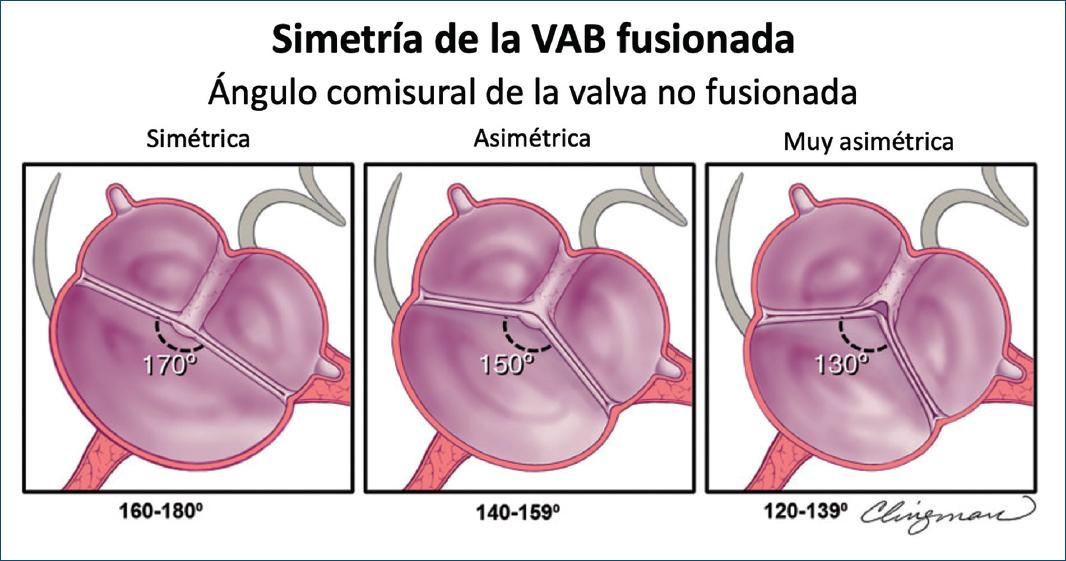

La simetría de la VAB para el tipo fusionado se define por el ángulo entre las comisuras de la cúspide no fusionada y recientemente se ha convertido en un aspecto crítico en la planificación de la reparación de la VAB para la insuficiencia aórtica pura6,20,44. Desde la perspectiva del tratamiento de la insuficiencia, el «concepto» de VAB ofrece una superficie de coaptación de una sola línea (una válvula aórtica tricúspide tiene tres líneas de coaptación [Fig. 5, izquierda]); siempre que esa única línea de coaptación sea recta o casi recta (Figs. 8 y 9-simétrica), la reparación de la VAB insuficiente es simple y reproducible. A medida que el ángulo entre las comisuras de la cúspide no fusionada disminuye < 160°44, la VAB se vuelve menos simétrica, pareciéndose más a una válvula tricúspide (especialmente < 140°) (Fig. 9, muy asimétrico), que se vuelve técnicamente más difícil para el cirujano «bicuspidizar» durante la reparación, pero sigue siendo reparable en manos experimentadas. Las válvulas asimétricas pueden exhibir retracción del borde libre de la cúspide fusionada a nivel del rafé, lo que se aprecia mejor mediante la visualización quirúrgica directa (Figs. 2 y 9) o inspección patológica, pero no se aprecia confiablemente por imágenes. Esta retracción puede contribuir a la insuficiencia de la válvula. La medición del ángulo comisural de la cúspide no fusionada con TEE antes de la derivación cardiopulmonar ayuda al cirujano a planificar la reparación (Fig. 10). Por lo tanto, la simetría de una VAB de tipo fusionado se define por el ángulo entre las comisuras de la cúspide no fusionada y es un parámetro crítico para la reparación quirúrgica de la VAB regurgitante.

Figura 9 Esquema de la evaluación ecocardiográfica transtorácica de la simetría de la válvula aórtica bicúspide (VAB) fusionada en eje corto paraesternal. Aplicable a vistas tomográficas similares obtenidas de la tomografía computarizada cardiaca y la resonancia magnética cardiaca, la figura demuestra diferentes ángulos comisurales de la cúspide no fusionados (aplicables a los tres fenotipos de la VAB fusionados, aunque solo se muestra la fusión de la cúspide derecha-izquierda) que definen la simetría. Panel izquierdo: VAB de fusión simétrica (ángulo 160-180°) derecha-izquierda con rafé, donde las dos cúspides funcionales son casi del mismo tamaño/forma (la cúspide no fusionada es un poco más grande) y el ángulo comisural de la cúspide no fusionada es de aproximadamente 170°. Panel central: VAB de fusión asimétrica (ángulo 140-159°) derecha-izquierda con rafé, y el ángulo comisural de la cúspide no fusionada es de aproximadamente 150°. Panel derecho: VAB de fusión derecha-izquierda muy asimétrica (ángulo 120-139°) que muestra retracción de la cúspide unida en el área del rafé y el ángulo comisural de la cúspide no fusionada es de aproximadamente 130°. Nótese que la retracción es más prominente a medida que el ángulo disminuye y que esto puede causar insuficiencia aórtica (modificada de Michelena et al., 20206 con permiso de Elsevier).